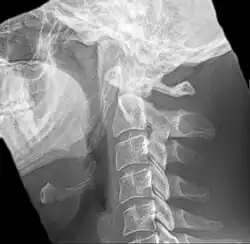

| Anteroposterior and lateral radiographs of cervical spine showing ossification of the stylohyoid ligament on both sides | |

Radiograph, lateral view showing elongated stylohyoid process and stylohyoid ligament ossification -

Radiograph, lateral view showing joint-like formation in ossified stylohyoid ligament -

Imaging is important and is diagnostic. Visualizing the styloid process on a CT scan with 3D reconstruction is the suggested imaging technique.[13] The enlarged styloid may be visible on an orthopantogram or a lateral soft tissue X ray of the neck.